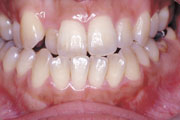

症例1:乱杭歯(叢生)